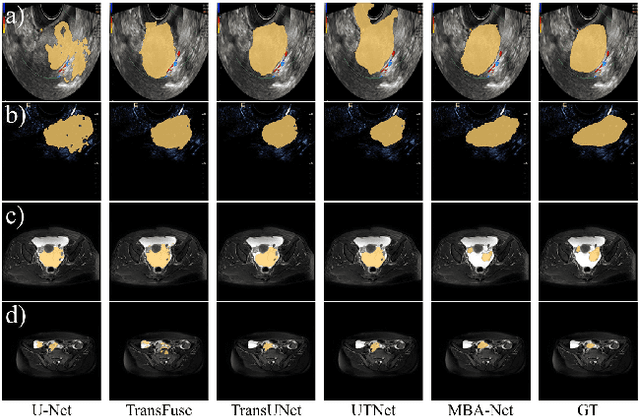

Abstract:Accurate segmentation of ovarian tumors from medical images is crucial for early diagnosis, treatment planning, and patient management. However, the diverse morphological characteristics and heterogeneous appearances of ovarian tumors pose significant challenges to automated segmentation methods. In this paper, we propose MBA-Net, a novel architecture that integrates the powerful segmentation capabilities of the Segment Anything Model (SAM) with domain-specific knowledge for accurate and robust ovarian tumor segmentation. MBA-Net employs a hybrid encoder architecture, where the encoder consists of a prior branch, which inherits the SAM encoder to capture robust segmentation priors, and a domain branch, specifically designed to extract domain-specific features. The bidirectional flow of information between the two branches is facilitated by the robust feature injection network (RFIN) and the domain knowledge integration network (DKIN), enabling MBA-Net to leverage the complementary strengths of both branches. We extensively evaluate MBA-Net on the public multi-modality ovarian tumor ultrasound dataset and the in-house multi-site ovarian tumor MRI dataset. Our proposed method consistently outperforms state-of-the-art segmentation approaches. Moreover, MBA-Net demonstrates superior generalization capability across different imaging modalities and clinical sites.